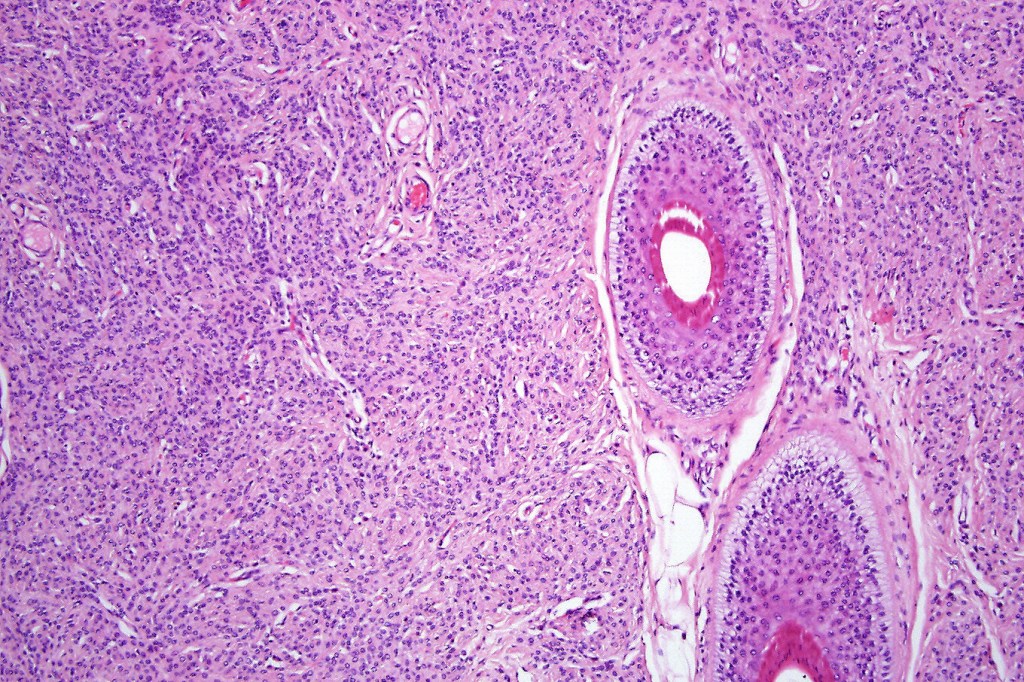

Histological features

•The nodule generally merges with the adjacent nevus but sometimes it can be sharply circumscribed

•It is hypercellular and most often composed of epithelioid cells showing little pleomorphism & only occasional mitoses

•Some examples show more marked pleomorphism with prominent nucleoli and increased mitotic activity but abnormal mitoses are not a feature. These are not associated with any sinister biological potential

•Absence of necrosis, hemorrhage or Pagetoid spread in the overlying epidermis

•Spindle cell, small blue cell, blue nevus-like features, Spitzoid & proliferative nodules with mesenchymal differentiation (myofibroblastic, chondroid & osteoid) can be seen